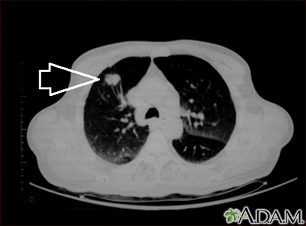

Masa pulmonar, lóbulo superior derecho - Tomografía computarizada

TC de la parte superior de los pulmones. El individuo posee una masa en la parte superior del pulmón derecho (lado izquierdo de la imagen).